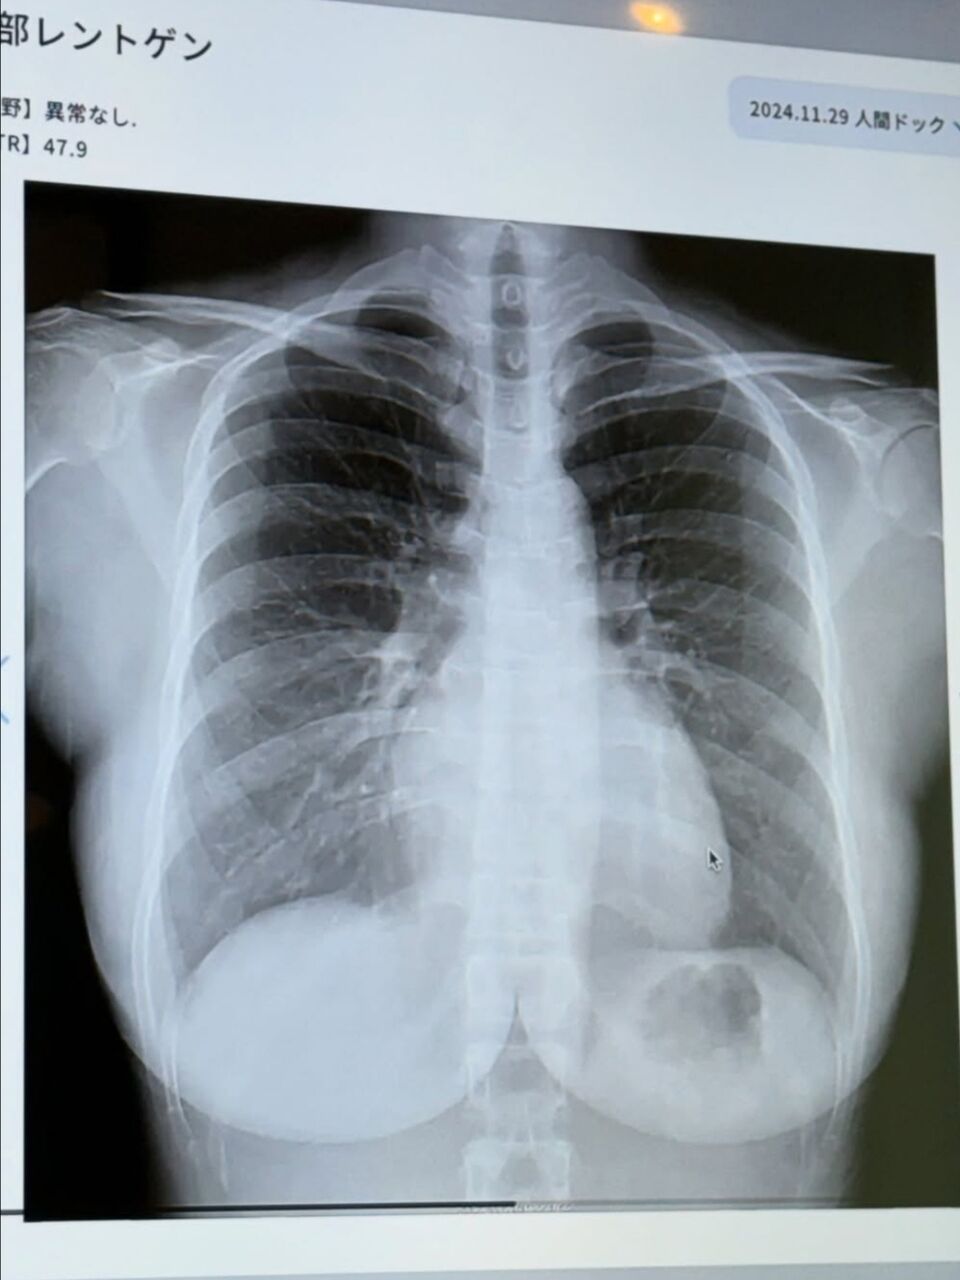

天木は「25歳ぶりに人間ドック 今年は肺のCTを撮った時の写真をお見せします!肺の上にぷるるんと天乳が見えますね」と胸部のエックス線写真を公開し「お腹減ってお胸は減らない 完璧です」とつづった。